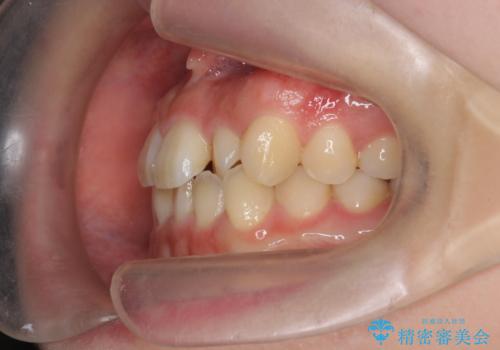

- ねじれの目立つ前歯を改善したいと、矯正治療を希望され来院されました。

インビザラインの不得意な上顎前歯のねじれの改善を、マウスピース矯正を行う前に前歯のみの部分ワイヤー矯正を行うことで治療期間の短期化を目指します。

上顎前歯のねじれはマウスピースで治りづらいため、マウスピース矯正の治療期間の長期化をきたしやすい歯列不正です。